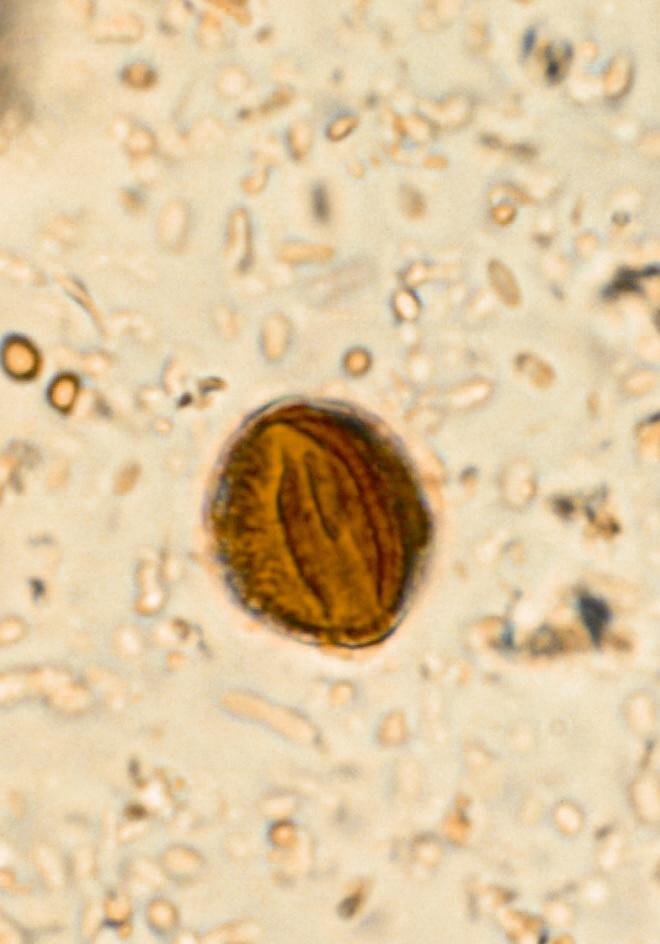

ภาพที่ 2. ภาพจากการตรวจอุจจาระของผู้ป่วยรายที่ 2.

ภาพที่ 3. ภาพจากการตรวจอุจจาระของผู้ป่วยรายที่ 2.

ชายอายุ 41 ปี มาพบแพทย์ด้วยอาการถ่ายเหลวมา 3 สัปดาห์ บางครั้งเห็นมูกเลือดปนอุจจาระ. ต่อมามีอาการปวดท้องเป็นๆ หายๆ น้ำหนักลด 2 กก.ใน 3 สัปดาห์ ไม่มีไข้. ตรวจร่างกายพบเพียงกดเจ็บเล็กน้อยทั่วๆท้อง. ตรวจอุจจาระพบดังภาพที่ 2 และ 3.

1. ผู้ป่วยที่มาด้วยอุจจาระร่วง 3 สัปดาห์และมีมูกเลือดปน จะต้องวินิจฉัยแยกโรคหลายโรค ซึ่งรวมถึงการติดเชื้อแบคทีเรีย เช่น shigellosis, salmonellosis, การติดเชื้อ Campylobacter หรือ E. coli เป็นต้น. การติดเชื้อไวรัส เช่น CMV การติดเชื้อปรสิต เช่น Entamoeba histolytica โรคใน กลุ่ม inflammatory bowel diseas และโรคในกลุ่มที่สัมพันธ์กับการใช้ยาต้านจุลชีพ (antibiotic-associated colitis). การตรวจอุจจาระด้วย fresh smear จะช่วยในการวินิจฉัยแยกโรคได้ในเบื้องต้น. จากภาพพบว่ามี cyst ที่มีลักษณะเข้าได้กับของ Entamoeba histolytica คือจะมี 4 nuclei เมื่อเป็น cyst ที่ mature แล้ว (ภาพที่ 3). การวินิจฉัยเบื้องต้นในรายนี้จึงน่าจะเป็น amoebic colitis. การตรวจเลือดหาแอนติบอดีต่อ Entamoeba histolytica มักจะให้ผลบวก (ร้อยละ 70).

2. ควรให้การรักษาด้วย metronidazole ในขนาด 500 มก. วันละ 3 ครั้ง นาน 10-14 วัน ติดตามผลการรักษาโดยดูจากอาการเป็นหลัก มักตอบสนองต่อการรักษาดี.